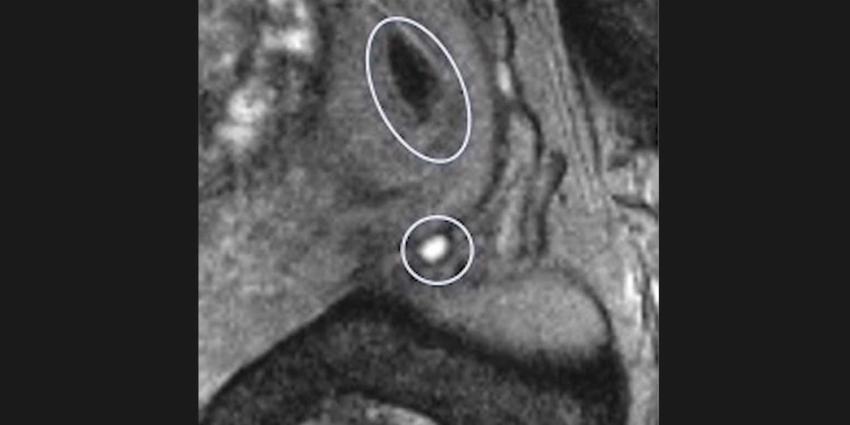

Contrastvloeistof ferrotran, een product van Radboudumc spin-off SPL Medical, maakt zeer kleine uitzaaiingen in de lymfeklieren heel goed zichtbaar op de MRI. Zelfs mini-uitzaaiingen van kleiner dan twee millimeter zijn ermee in beeld te brengen. Het middel bestaat uit nano-ijzerdeeltjes, die normale lymfklieren op een MRI ‘zwart’ maken, terwijl afwijkende kliertjes wit kleuren. Hierdoor kunnen ze zeer goed van elkaar worden onderscheiden.

Omdat ferrotran ook de lymfevaten zichtbaar maakt, kunnen de mini-uitzaaiingen ook uitstekend worden gelokaliseerd. Dat maakt behandeling - bijvoorbeeld gerichte bestraling - in een vroege fase mogelijk, waardoor er minder bijwerkingen zijn en de kans op genezing toeneemt. Andere diagnostische technieken krijgen dergelijke kleine uitzaaiingen niet in beeld. Bij die technieken is vier tot zes millimeter de grens.